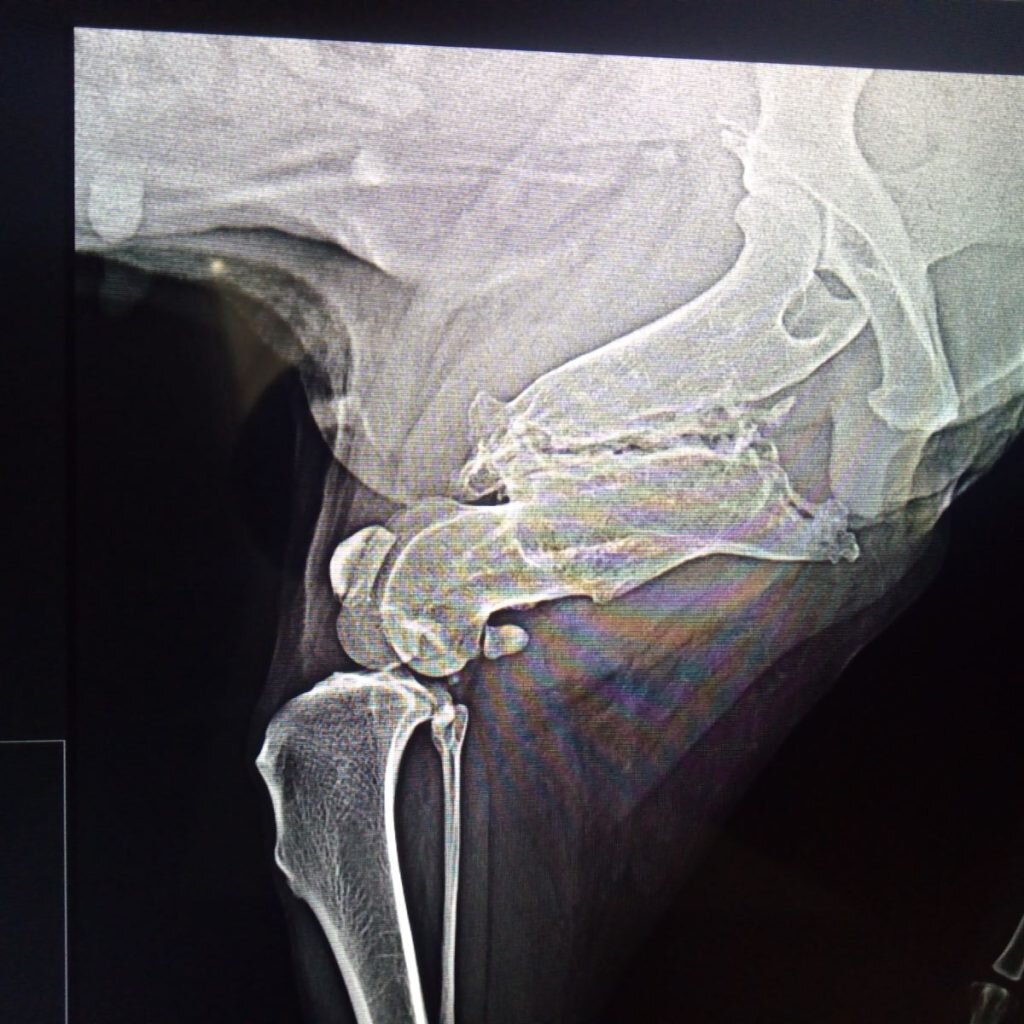

Нарушения целостности структур опорно-двигательного аппарата без своевременного и качественного лечения практически всегда приводят к осевым деформациям костей, замедленному сращению переломов или неправильному заживлению с формированием ложных суставов, укорочением конечности, болезненности, хроническому дискомфорту и пожизненной хромоте (рис.2). Помимо этого, в зонах патологического не срастания переломов может сохраняться хронический, воспалительный процесс, являющийся своего рода мишенью для «атаки» микроорганизмов или очагами для роста опухолей

Рис.2 Застарелый перелом бедренной кости у собаки.